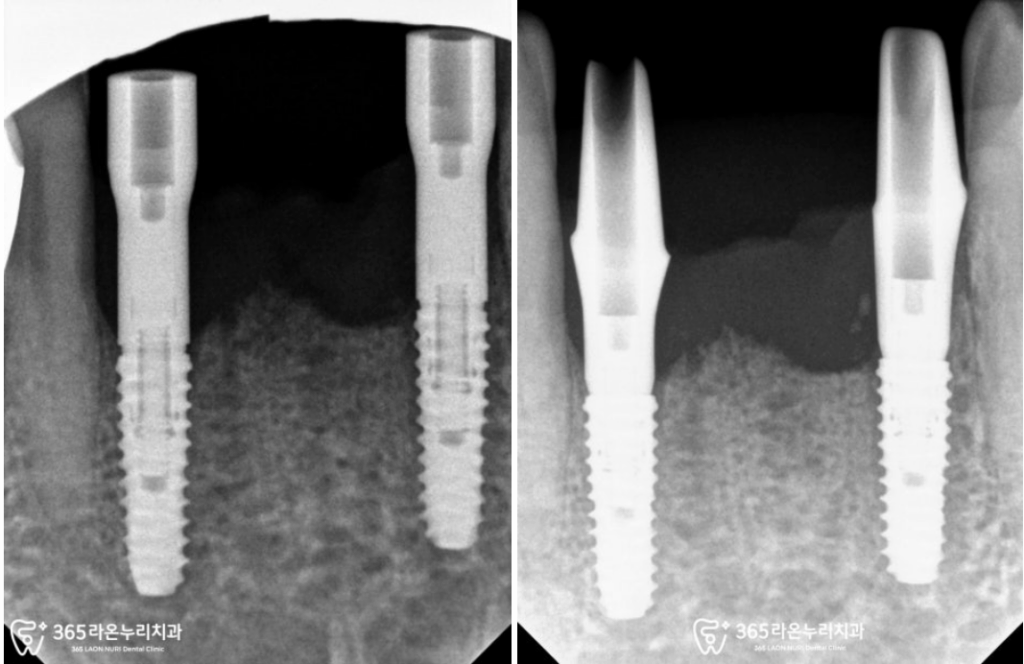

아래 앞니 브릿지 제작을 위해

두 개의 임플란트 픽스처를

의도한 곳에 잘 식립한 모습입니다.

아랫니의 경우에는 심미적으로 민감한

부위이기 때문에 이어서

인상 채득을 진행하기로 했습니다.

당일 수술 후 고정력이 좋았어서,

오산 신장동 치과 에서는 즉시

커스텀(Custom Abut) +

PMMA 임시 제작에

들어가게 되었습니다.